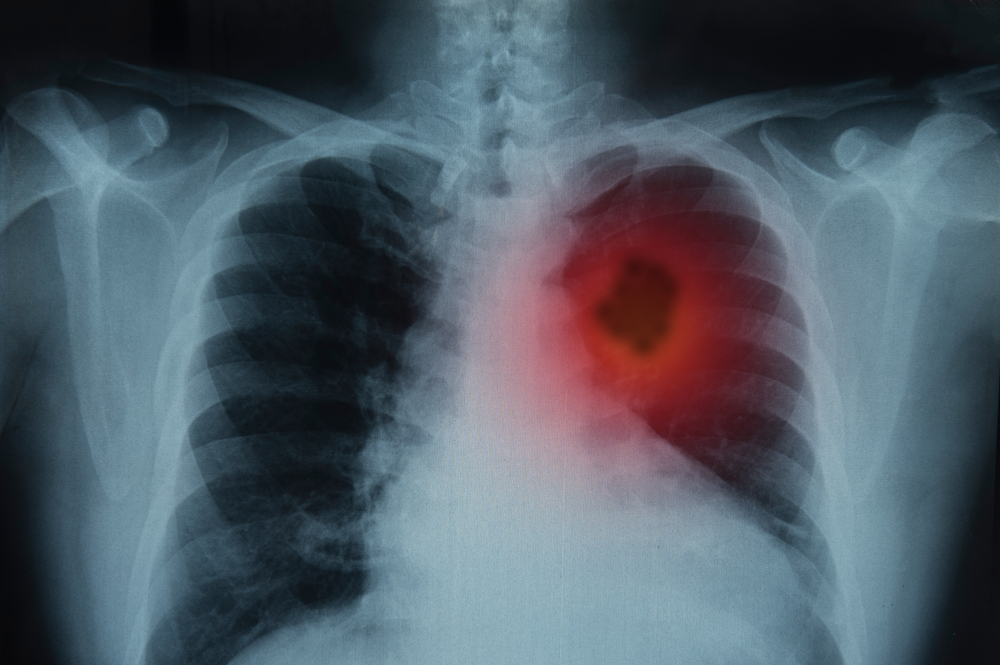

- Рентгенография органов грудной клетки (позволяет выявить патологический очаг либо косвенные признаки, указывающие на наличие опухоли).

- Компьютерная томография (дает возможность выявить даже небольшие опухоли, детально изучить подозрительный участок легочной ткани, оценить состояние бронхиального дерева, характер опухоли и ее распространение на окружающие ткани).